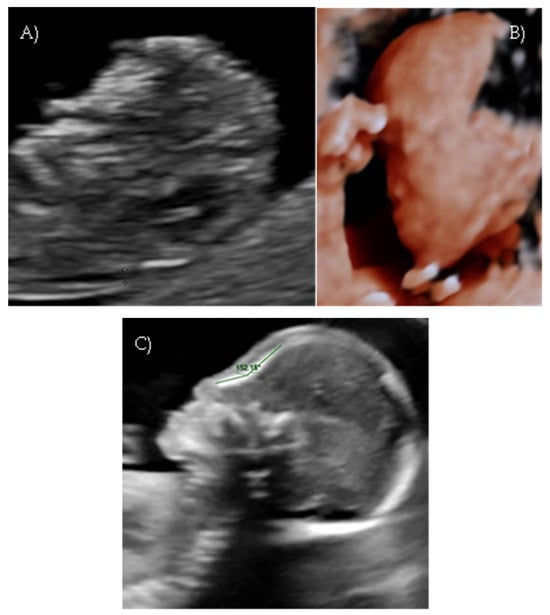

During the first-trimester scan a flat fetal profile was noted and suspected of indicating a fetal abnormality, and early re-evaluation of the fetal craniofacial anatomy was recommended (Figure 2A).

At 17 weeks and 4 days of gestation, follow-up ultrasound confirmed a flattened fetal facial profile consistent with Binder-type maxillonasal dysplasia (Figure 2B,C). Other fetal anatomy findings appeared normal.

Figure 2. Case 2. (A) First-trimester 2D ultrasound fetal profile. (B) Flat fetal profile, 3D reconstruction, at 17 + 4 w. (C) Flat fetal profile, 17 + 4 w.